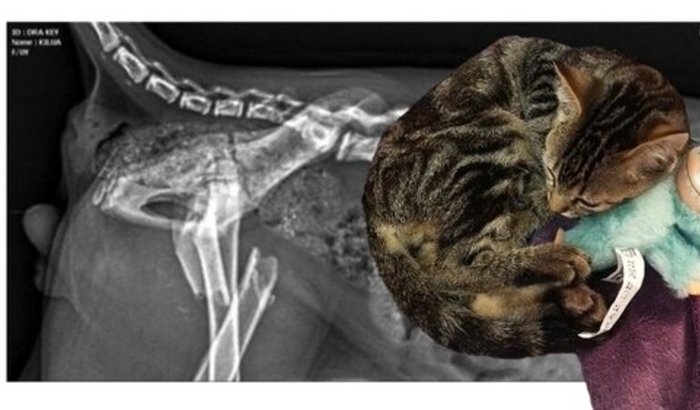

Recentemente adotei um gatinho bebê (2 Meses), e desde o primeiro momento ele mancava muito, mas aparentemente sem dor ou algum tipo de 'dificuldade' além. Imediatamente procurei um veterinário, e através do exame de Raio X descobrimos uma fratura completa que tanto pela idade, quanto pela gravidade da situação, foi considerado um caso urgente com risco de fratura exposta enquanto não é realizado a cirurgia. Como foi uma situação muito inesperada não consigo arcar com os custos sozinha e de forma imediata, pois os custos da cirurgia totalizam aproximadamente R$4.000,00.